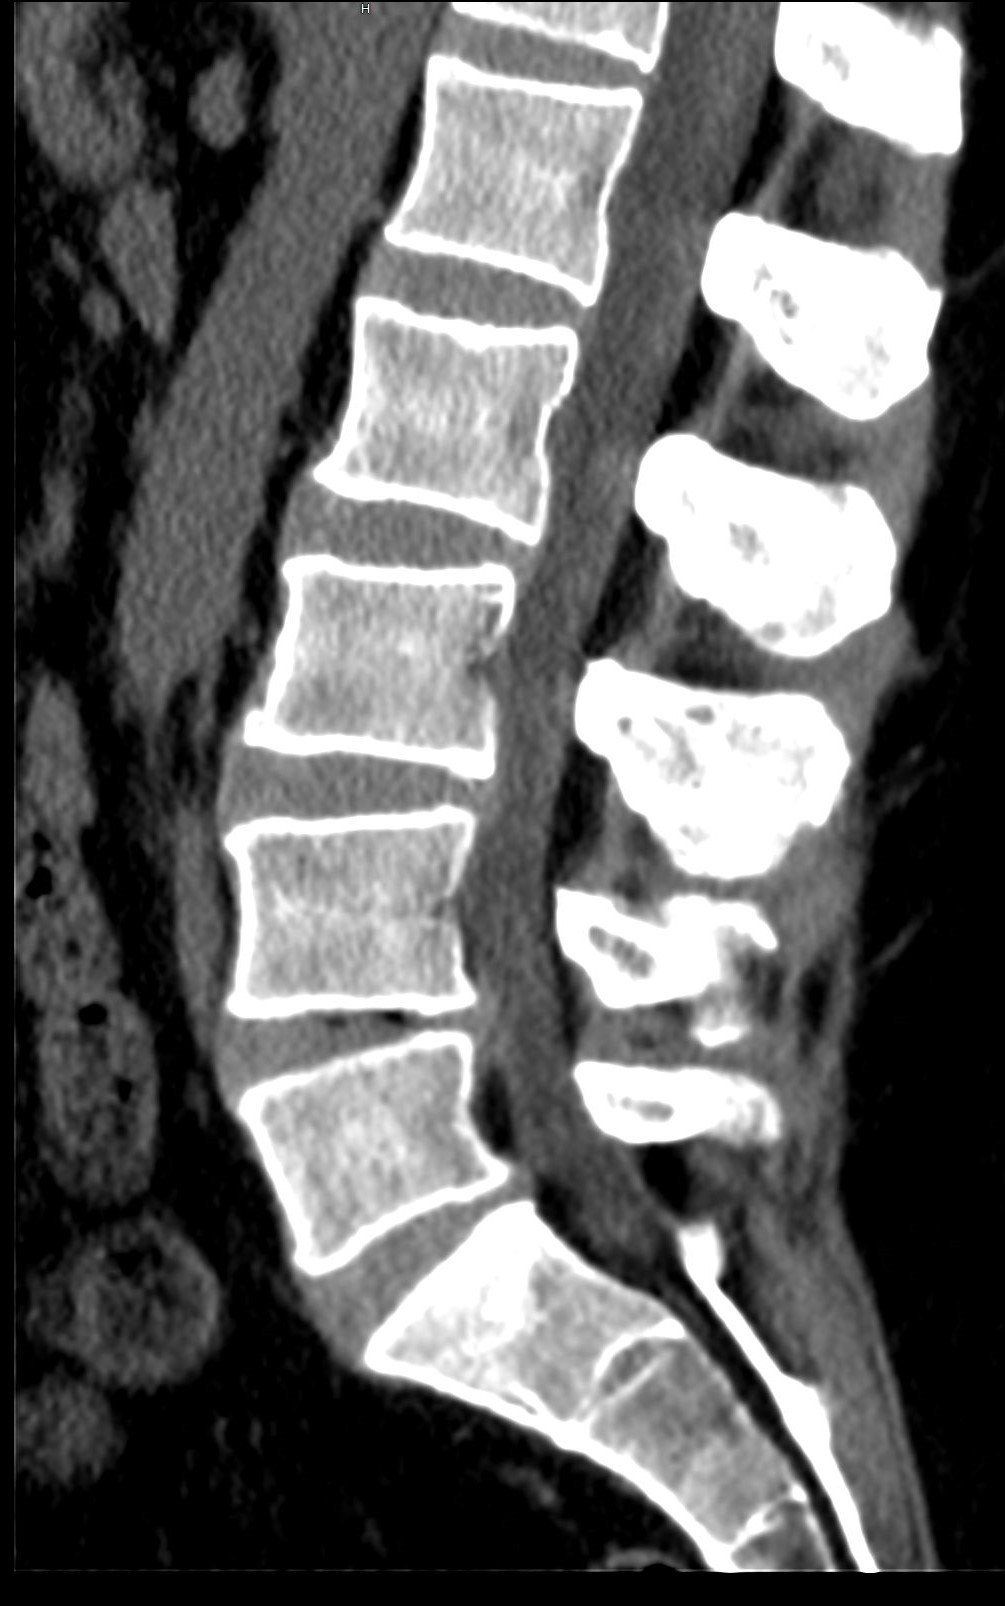

DEPISTAGE DU CANCER DU POUMON

Nous sommes équipés de

deux scanners faible dose, de dernière génération, dotés d’intelligence artificielle permettant de dépister précocement les nodules suspects.

Plusieurs essais cliniques contrôlés randomisés de grande envergure ont montré

l’efficacité du scanner thoracique faible dose pour le dépistage des cancers des poumons chez les fumeurs et anciens fumeurs, permettant, lorsqu’il est associé à une incitation au sevrage tabagique, une diminution significative de la mortalité spécifique par cancer du poumon.